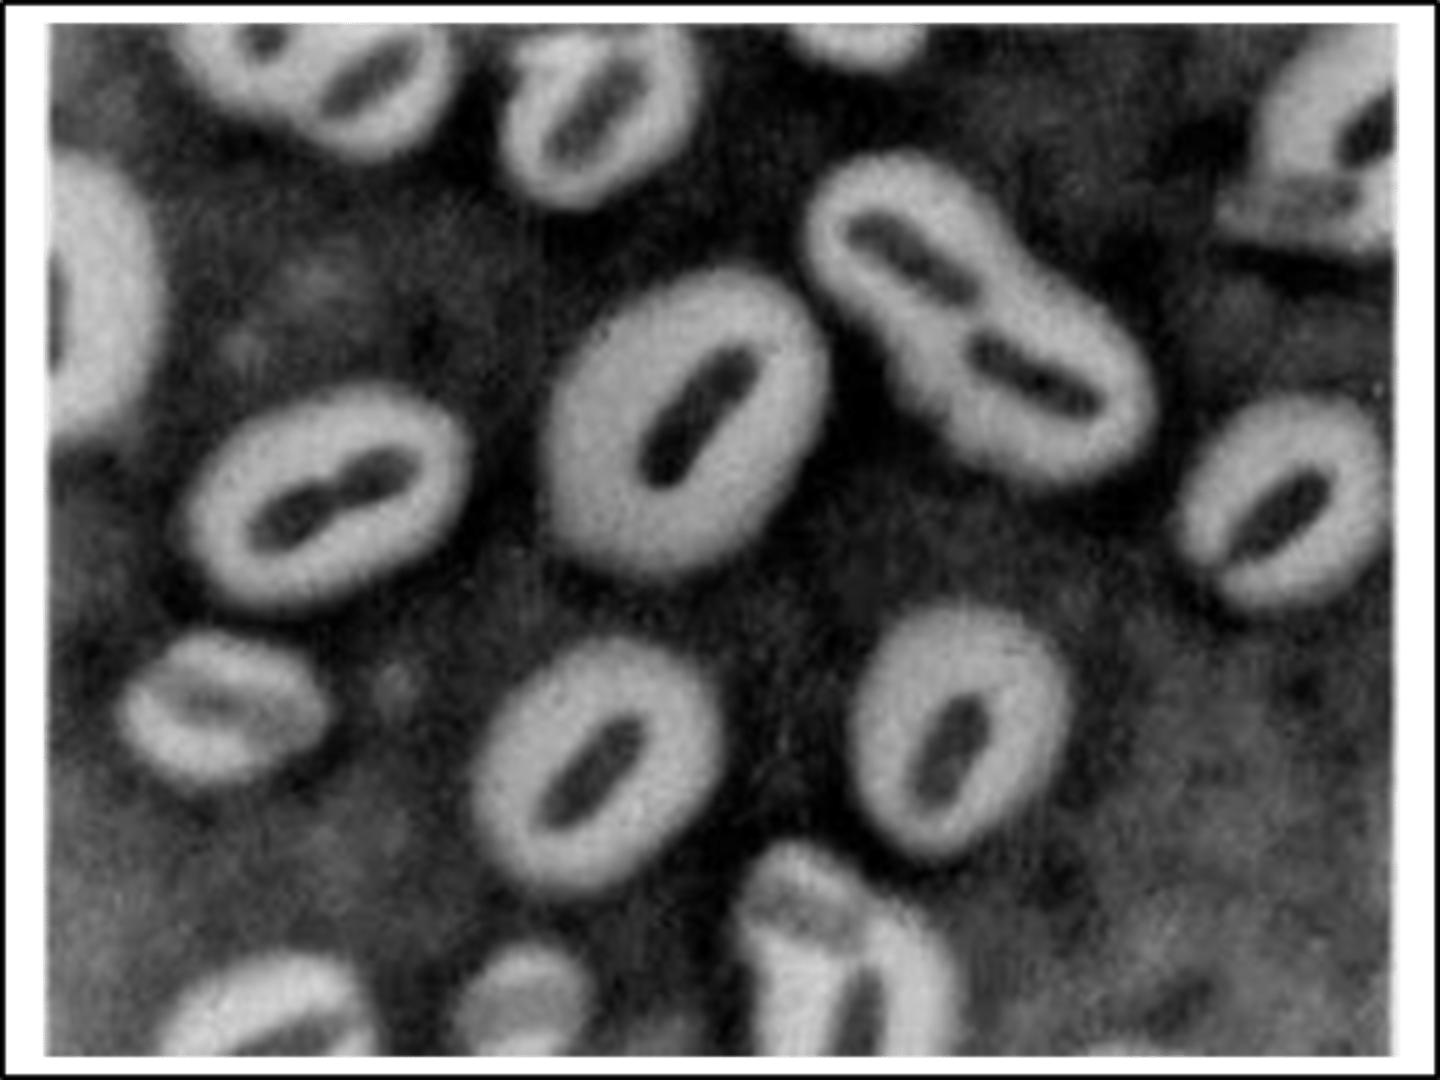

Dermatophilus congolensis

Several scabs were collected and submitted for examination from a Holstein cow with raised scabs covering 20 to 30% of the back. Examination revealed a mild-moderate exudative dermatitis beneath the scabs. The scabs are 1-2 cm in diameter and with the hair entrapped, resemble a paintbrush when viewed from the side.

It did not grow on SDA or MAC

It appears on gram stain with gram+ branching filaments and a "train track" morphology